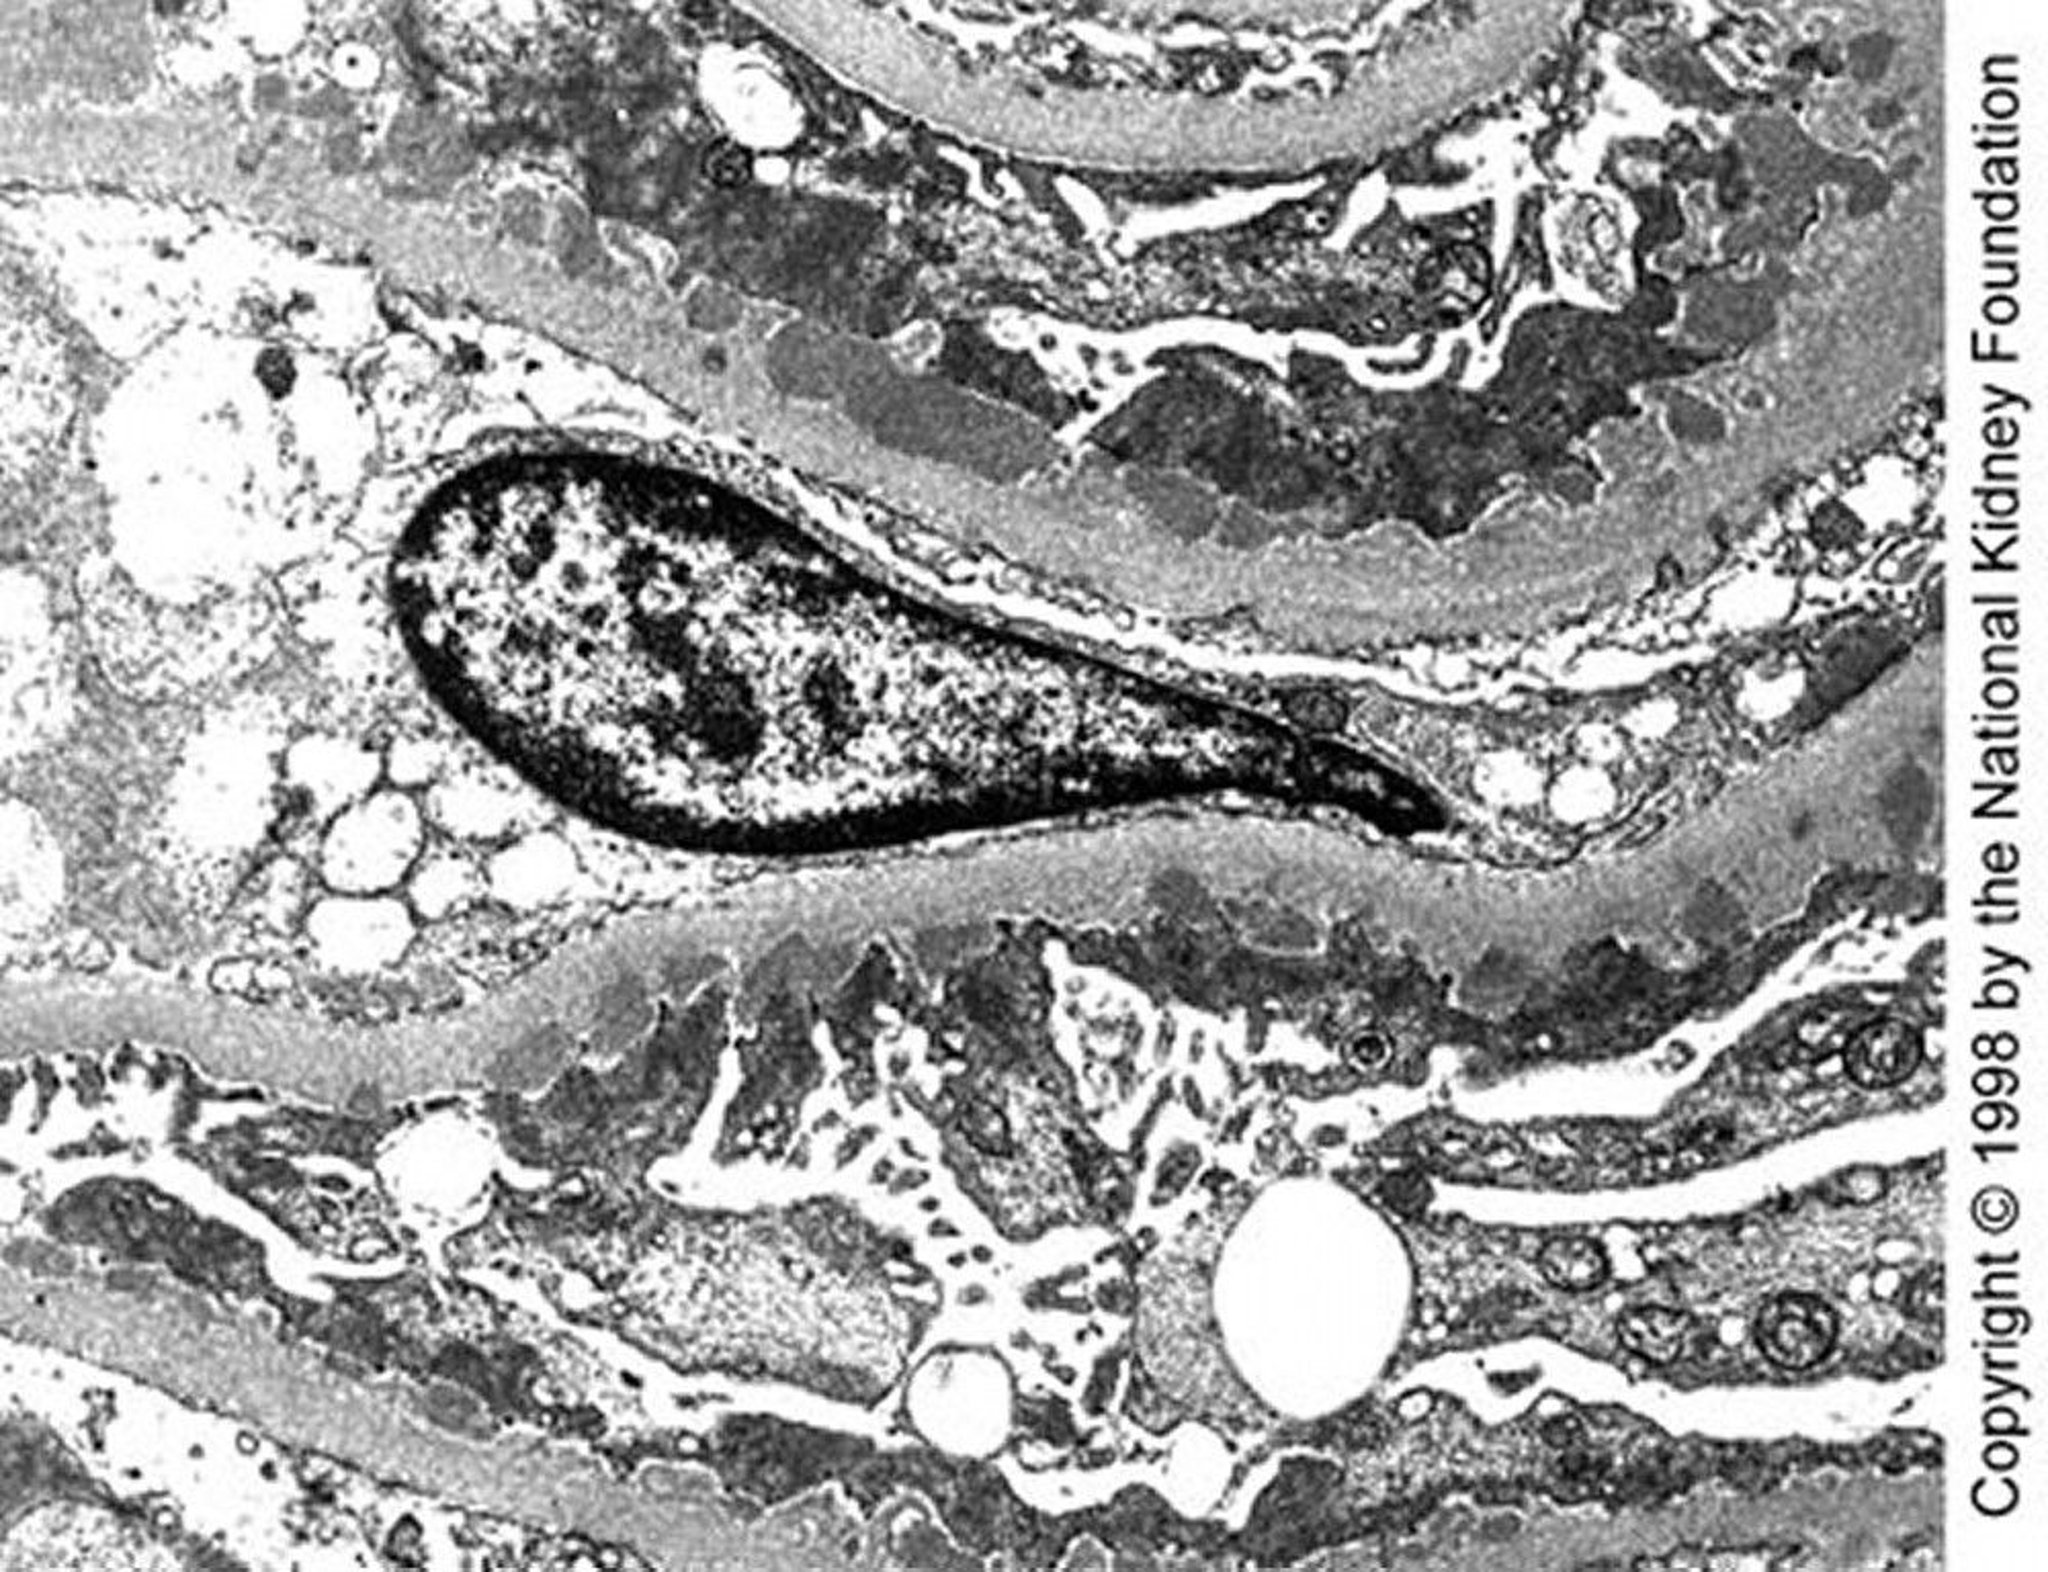

Membranous Nephropathy (Dense Deposits)

Medium-sized subepithelial dense deposits are seen on transmission electron microscopy in late stage I disease (×10,200).

Image provided by Agnes Fogo, MD, and the American Journal of Kidney Diseases' Atlas of Renal Pathology (see www.ajkd.org).